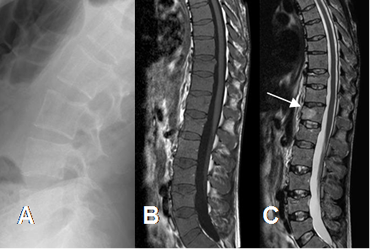

Fig 196. Mieloma.

A: Rx lateral. Osteoporosis generalizada, sin lesiones focales.

B: RM sagital en T1 y C: RM sagital en STIR. Completa reconversión a medula roja en los cuerpos vertebrales, con lesión focal y aguda en D12.